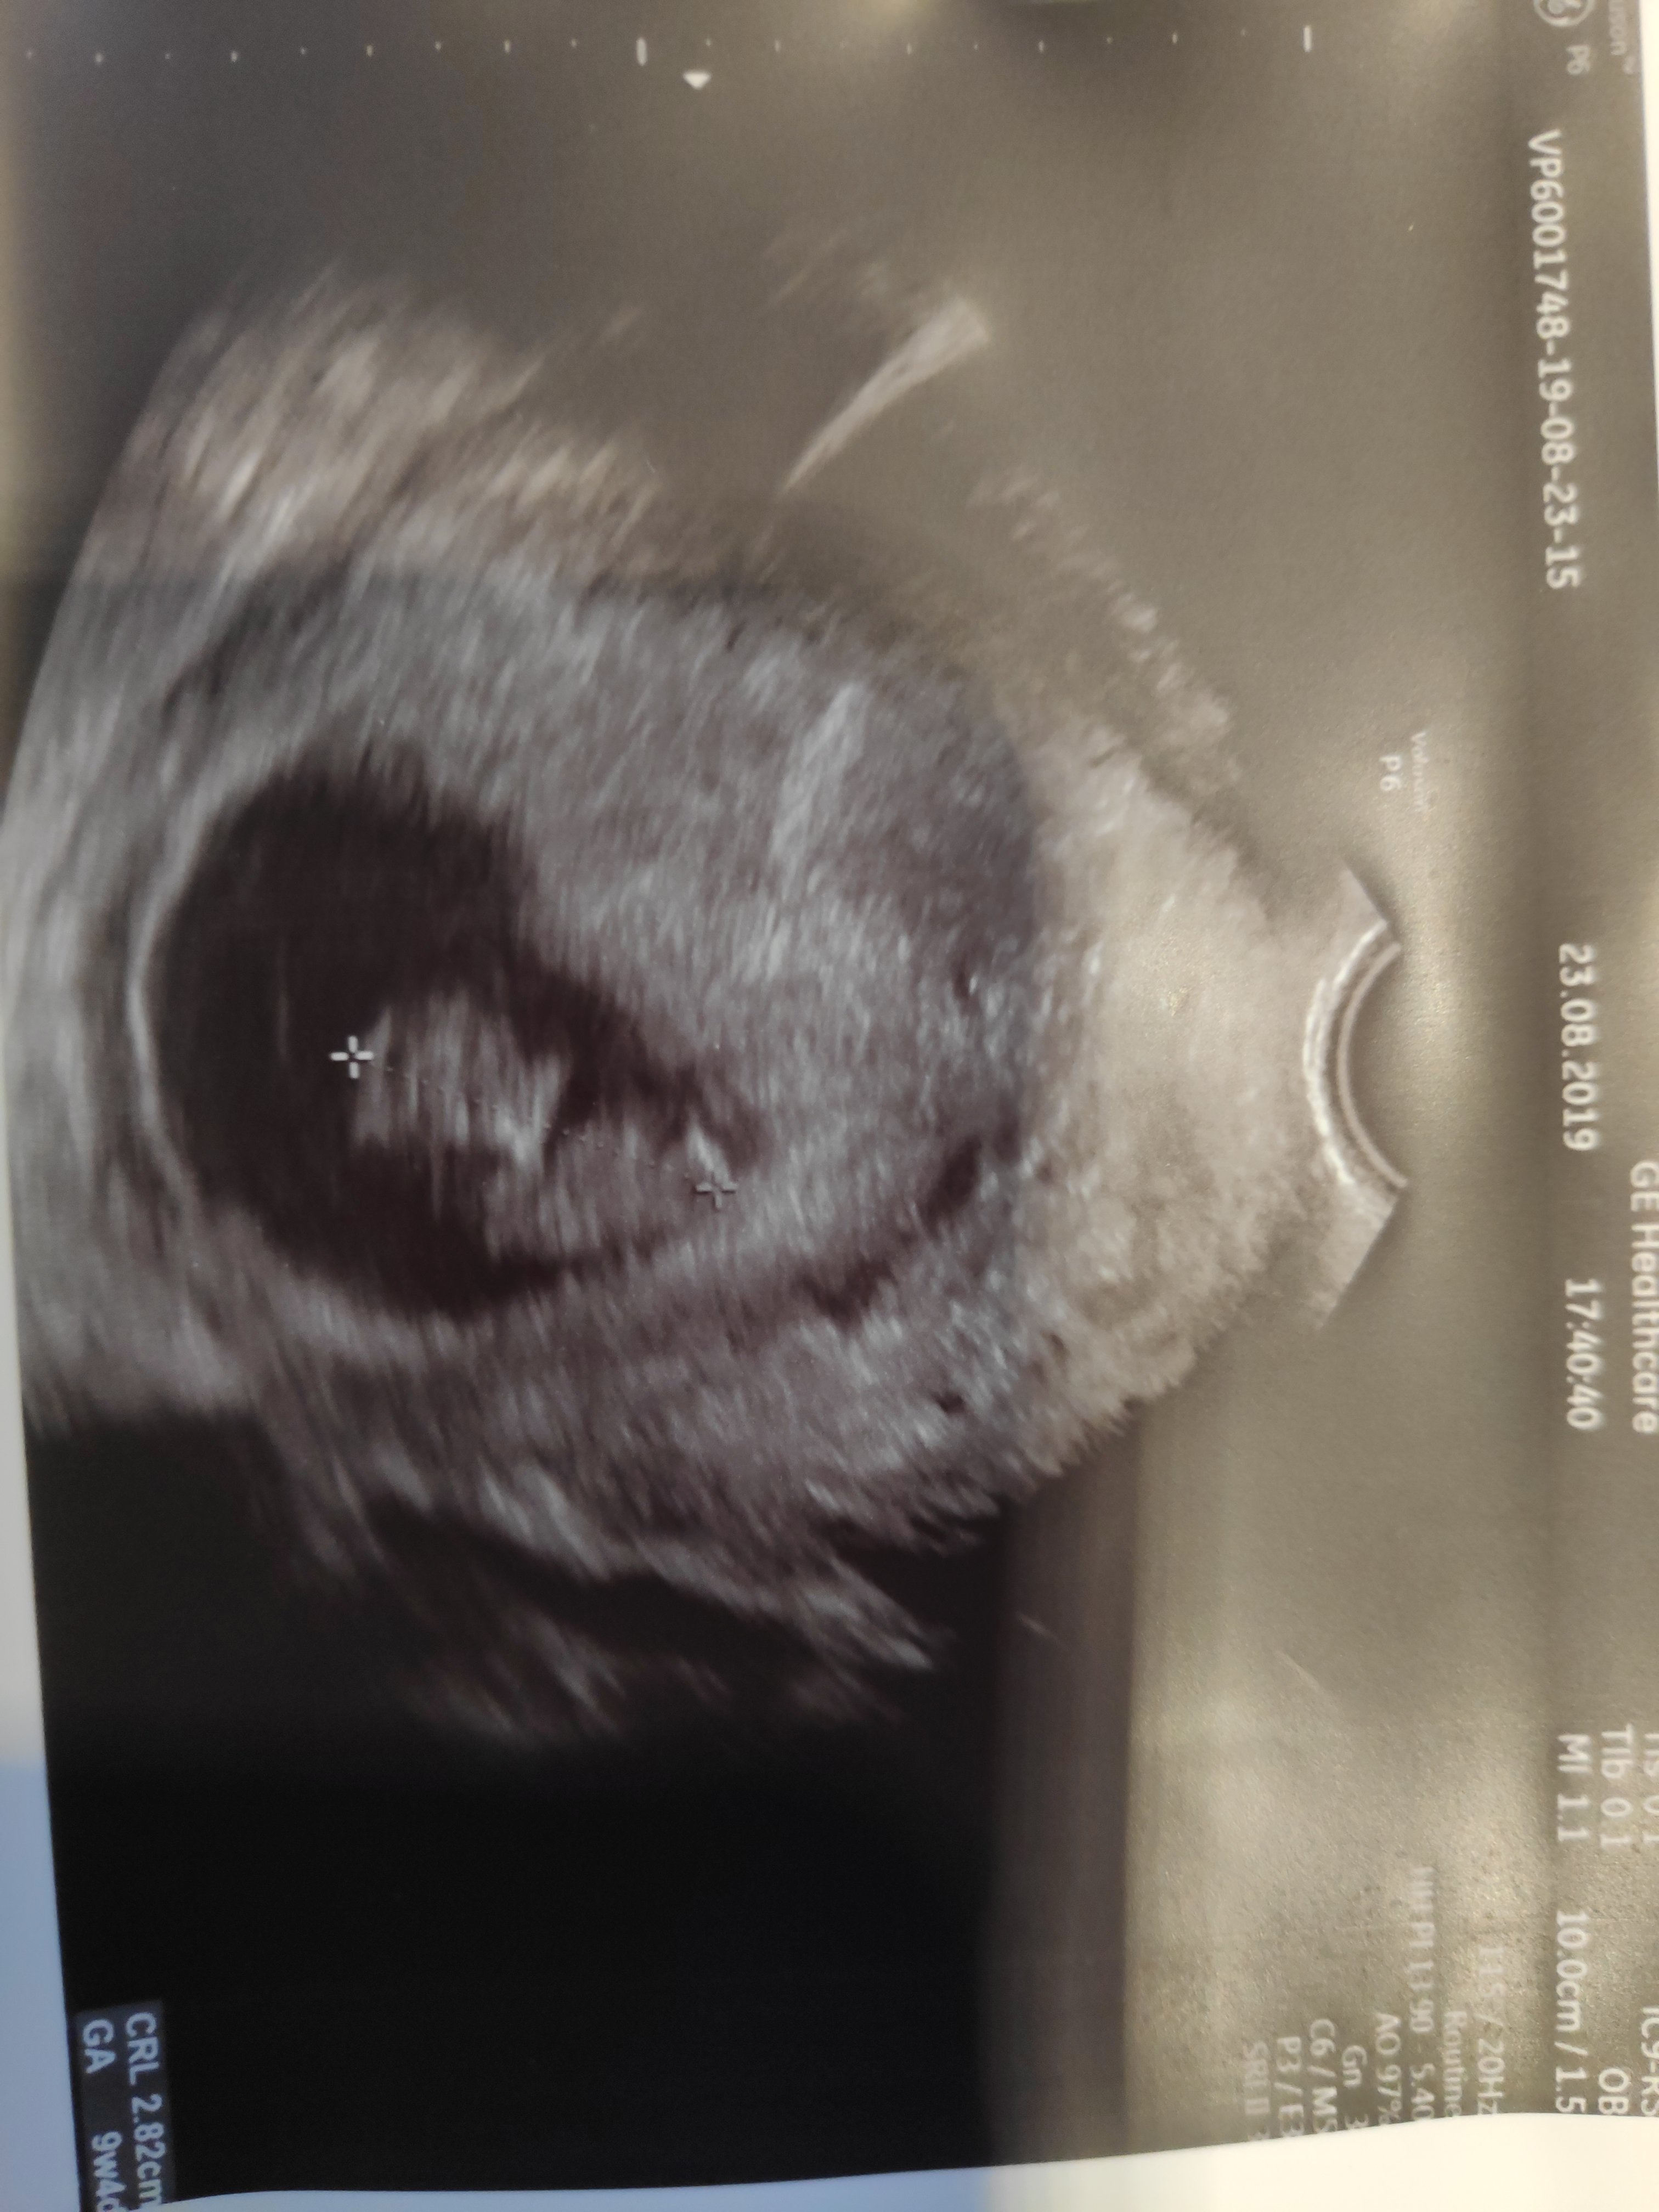

Dzidzia (sorry @agacior89 , to ostatni raz :D) ma juz 2.9cm, 9t4d, termin mam na 26 marca. Ogolnie to jestem zachwycona, bo znalazlam fajny osrodek poloznych, w ktorym maja swietny sprzet. Wszystko bylo pieknie widac, 2d, 3d, slyszalam bicie serca i dostalam plytke ze zdjeciami i filmem. Maluszek doslownie skalal w brzuchu.

Podpytalam tez polozna jak to jest z biciem serca, bo licze na dziewczynke a 189 daje mi nadzieje :D Powiedziala, ze slyszala o tej teorii, ale ona w praktyce sprawdza sie dopiero od 24 tygodnia ciazy.